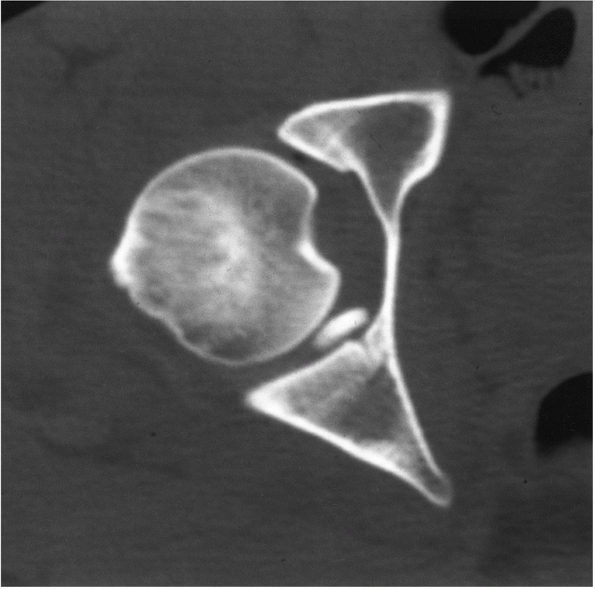

The CT scan is more sensitive in detecting small intra-articular

fragments, femoral head fractures, femoral head impaction injuries,

acetabular fractures, and joint incongruity.5,36,46,100,119,158,192 It has been demonstrated that intra-articular fragments are better visualized on CT than plain films. Hougaard et al.67

congruence of the hip is also easily evaluated using CT. The head

should be in the center of the subchondral ring of the acetabulum as it

becomes visible, appearing as a bullseye.173

A difference of as small as 0.5 mm in the distance from the anterior,

articular surface to the femoral head has been reported to indicate a

subluxation of the hip.18 Impaction

injuries and femoral head fractures are much more easily seen on the

postreduction CT. The quality of the reduction of femoral head